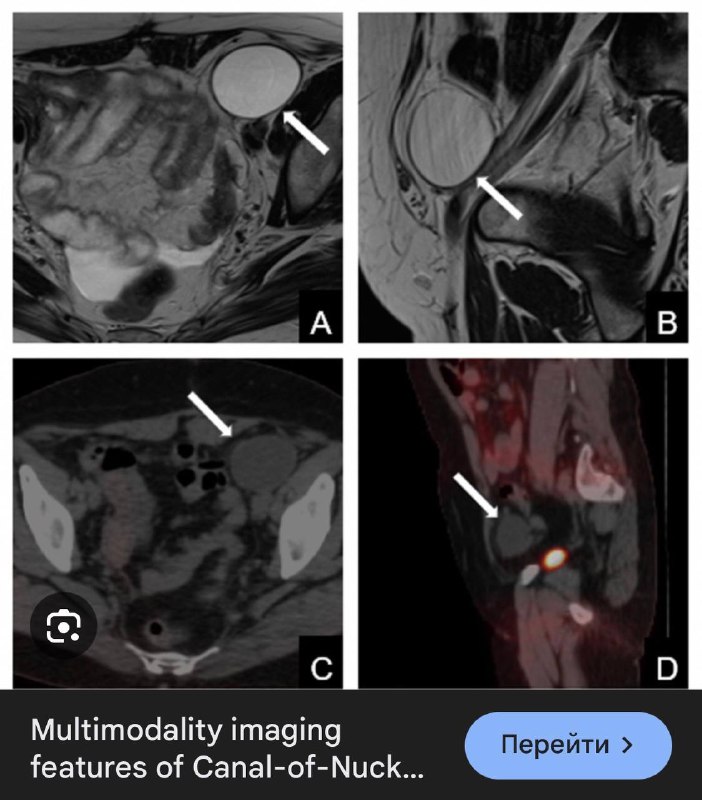

В 1691 году Антон Нук, голландский анатом, был первым, кто описал этот канал, который сейчас назван его именем. Канал Нука является женским эквивалентом вагинального отростка у мужчин, который обычно исчезает в течение первого года жизни. Он состоит из складки, выпячивания брюшины, которая прикрепляется к матке круглой связкой и проходит через паховое кольцо вдоль круглой связки в большие губы. Обычно верхняя часть этого выпячивания обтурируется во время рождения или непосредственно перед ним и исчезает в течение первого года жизни. В редких случаях эта обтурация не завершатся, что приводит к сохранению канала Нука и может вызвать образование женского гидроцеле, а именно кисты канала Нука.

Видимо, в зависимости от того, проксимально или дистально и на каком протяжении просвет канала остается открытым, такой протяженности и локализации и формируется его киста.

В нашем случае, скорее всего, киста сформировалась лишь в проксимальных отделах этого канала, а перегородки и неправильная форма могут служить признаком перенесённых травматизации или воспалений. Клинически никак не проявляется, случайно обнаружена на УЗИ, по всей видимости, потому, что не ущемляется в канале и никак снаружи не пальпируется.

А может это и лимфатическая мальформация. В любом случае, верификация вряд ли будет, но узнать о кисте канала Нука всегда полезно тем, кто о ней никогда не слышал. Пусть эта штука послужит тем замечательным поводом.